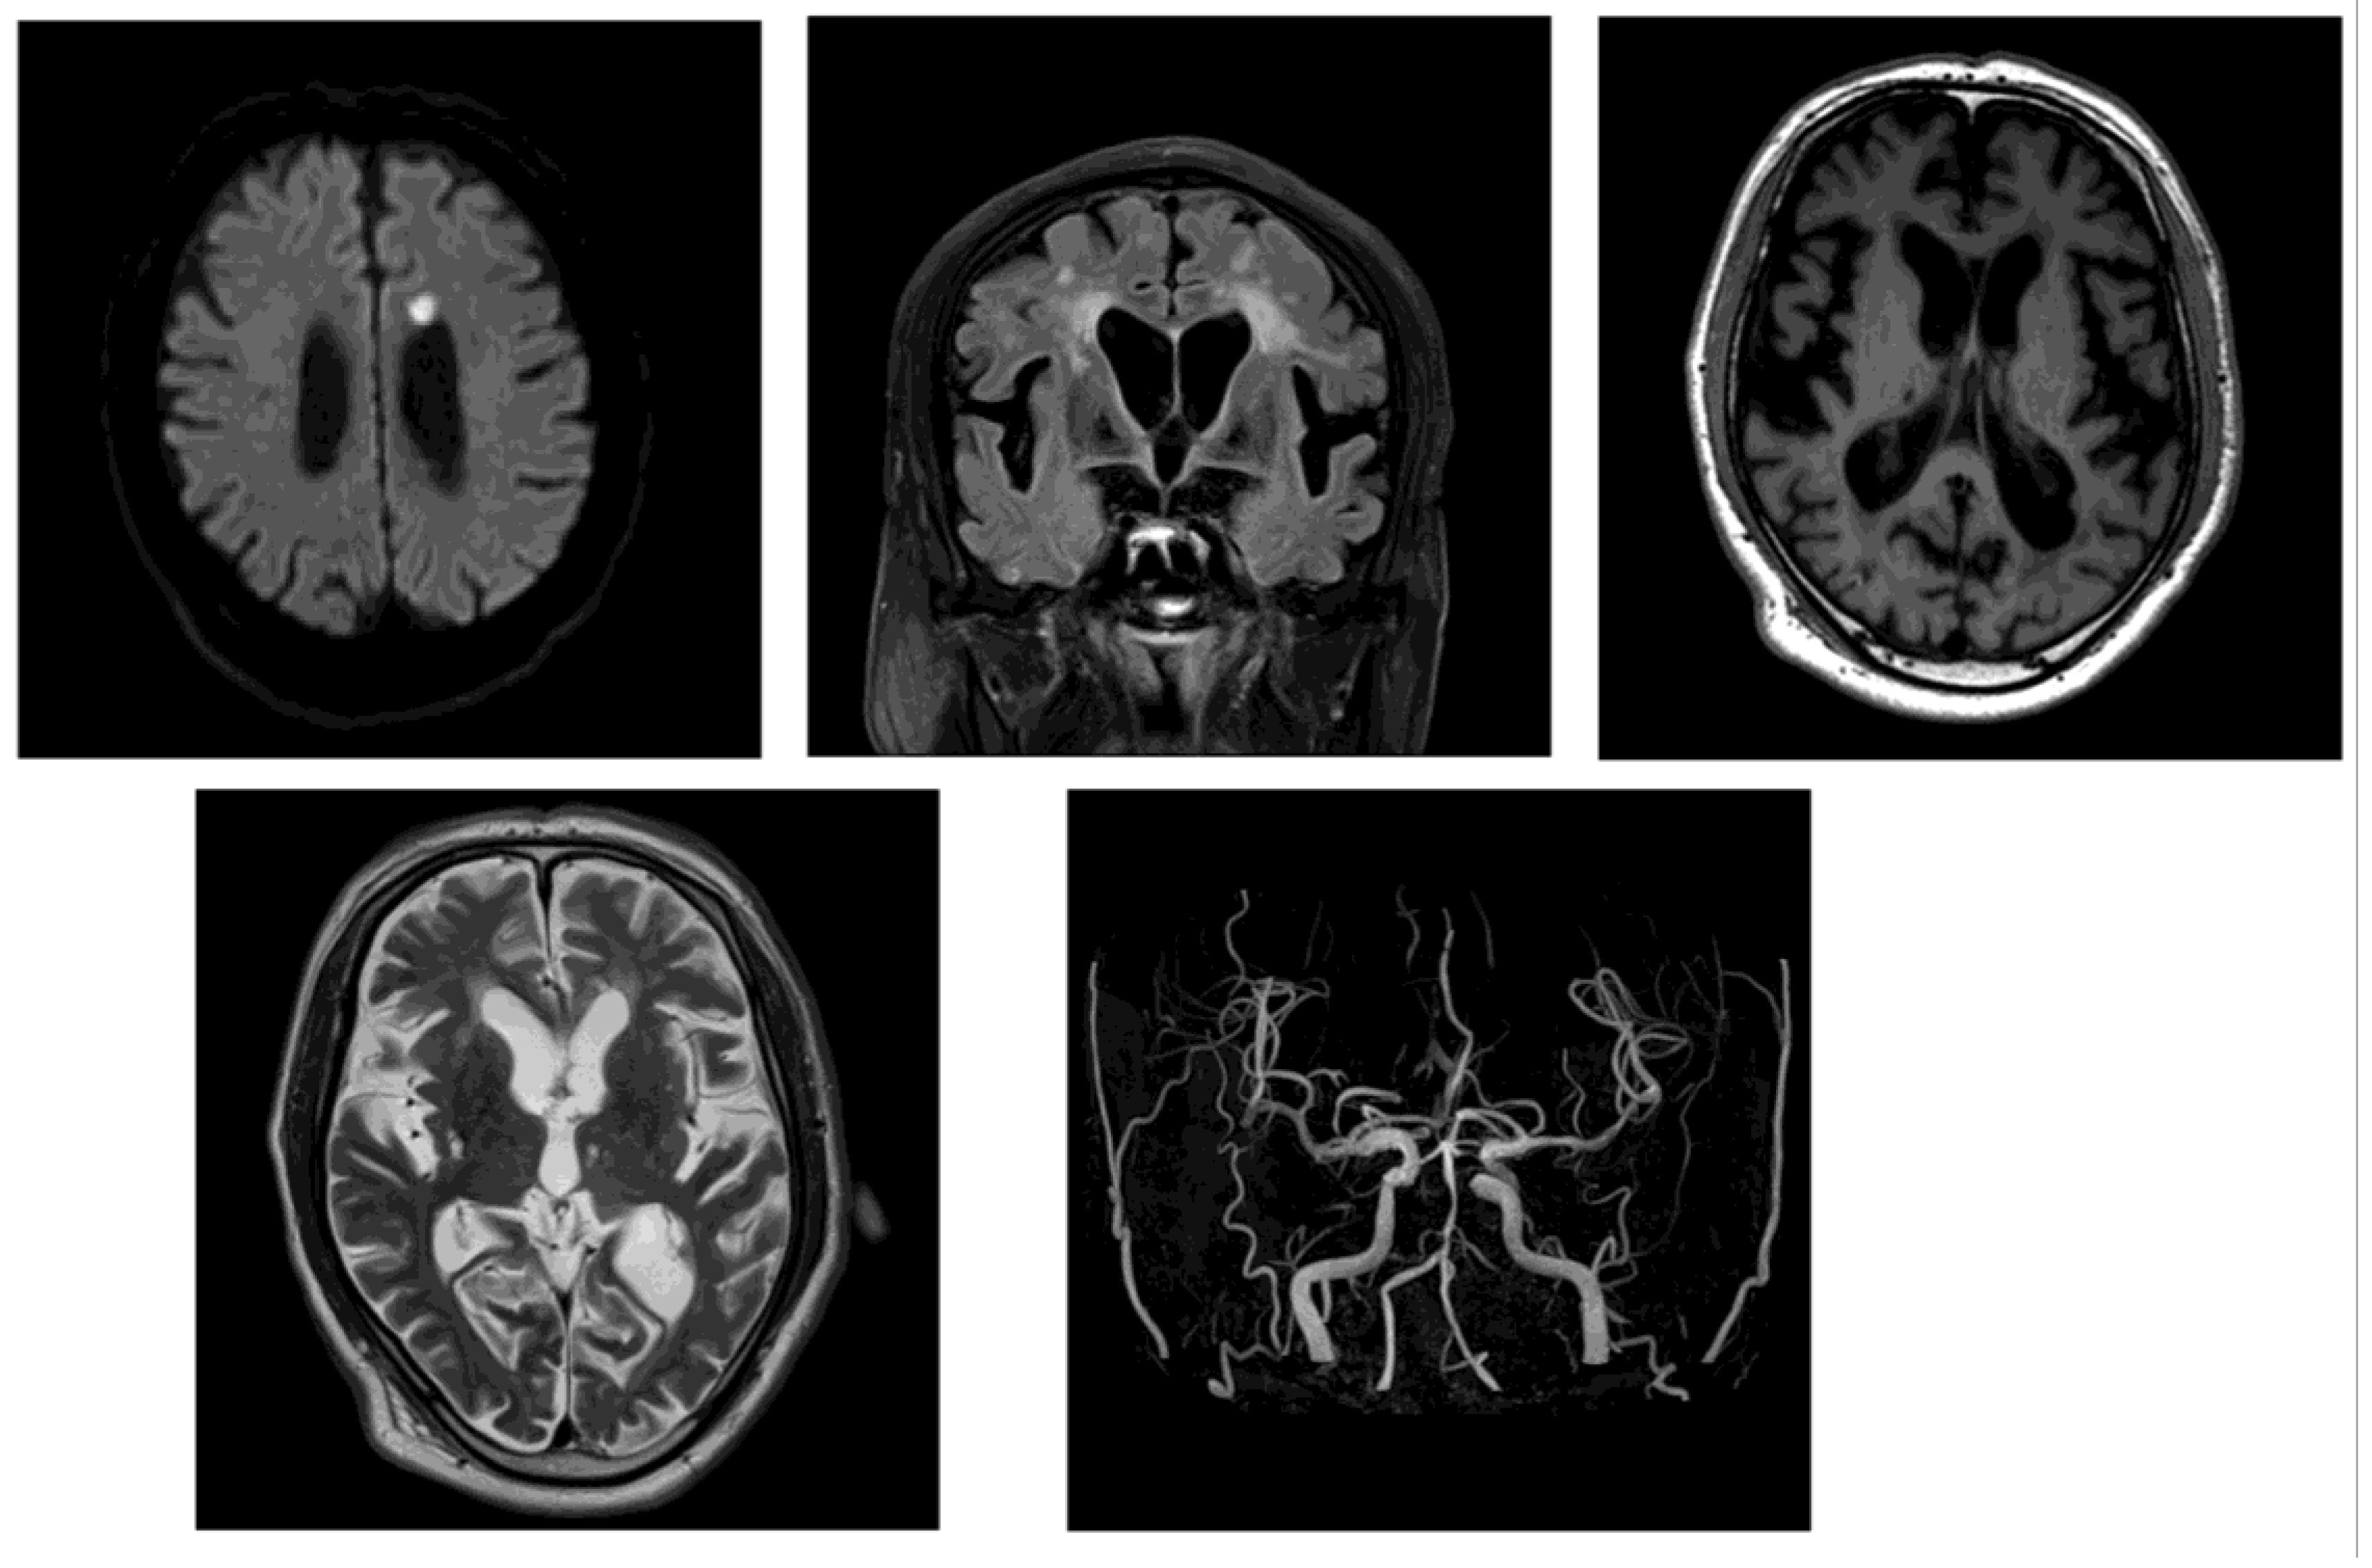

On day 2, brain magnetic resonance imaging (MRI) showed no signs of acute cerebral infarction; however, chronic lacunar infarcts were present, alongside periventricular white matter changes. No arterial or venous thrombosis, or stenosis, was observed (Figure 2).

Figure 2. MRI on day 2 of Case 1’s hospitalization, showing chronic ischemic changes. T2-weighted and FLAIR sequences revealed chronic lacunar infarcts and periventricular white matter hyperintensities. No acute ischemic lesions or vascular stenosis was observed.